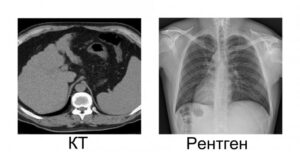

КТ или рентген: сравнение, радиационная нагрузка, преимущества и недостатки методов лучевой диагностики

Рентгенологическая диагностика — это первый метод визуализации органов при жизни, используемый в медицине. Методы лучевой диагностики — компьютерная томография и рентген. Рентген дешевле и менее опасен, а томография более точна и информативна. Только врач, зная течение и клиническую картину заболевания, может решить, какое обследование лучше — компьютерная томография или рентген. Различия в основных рентгенологических методах …